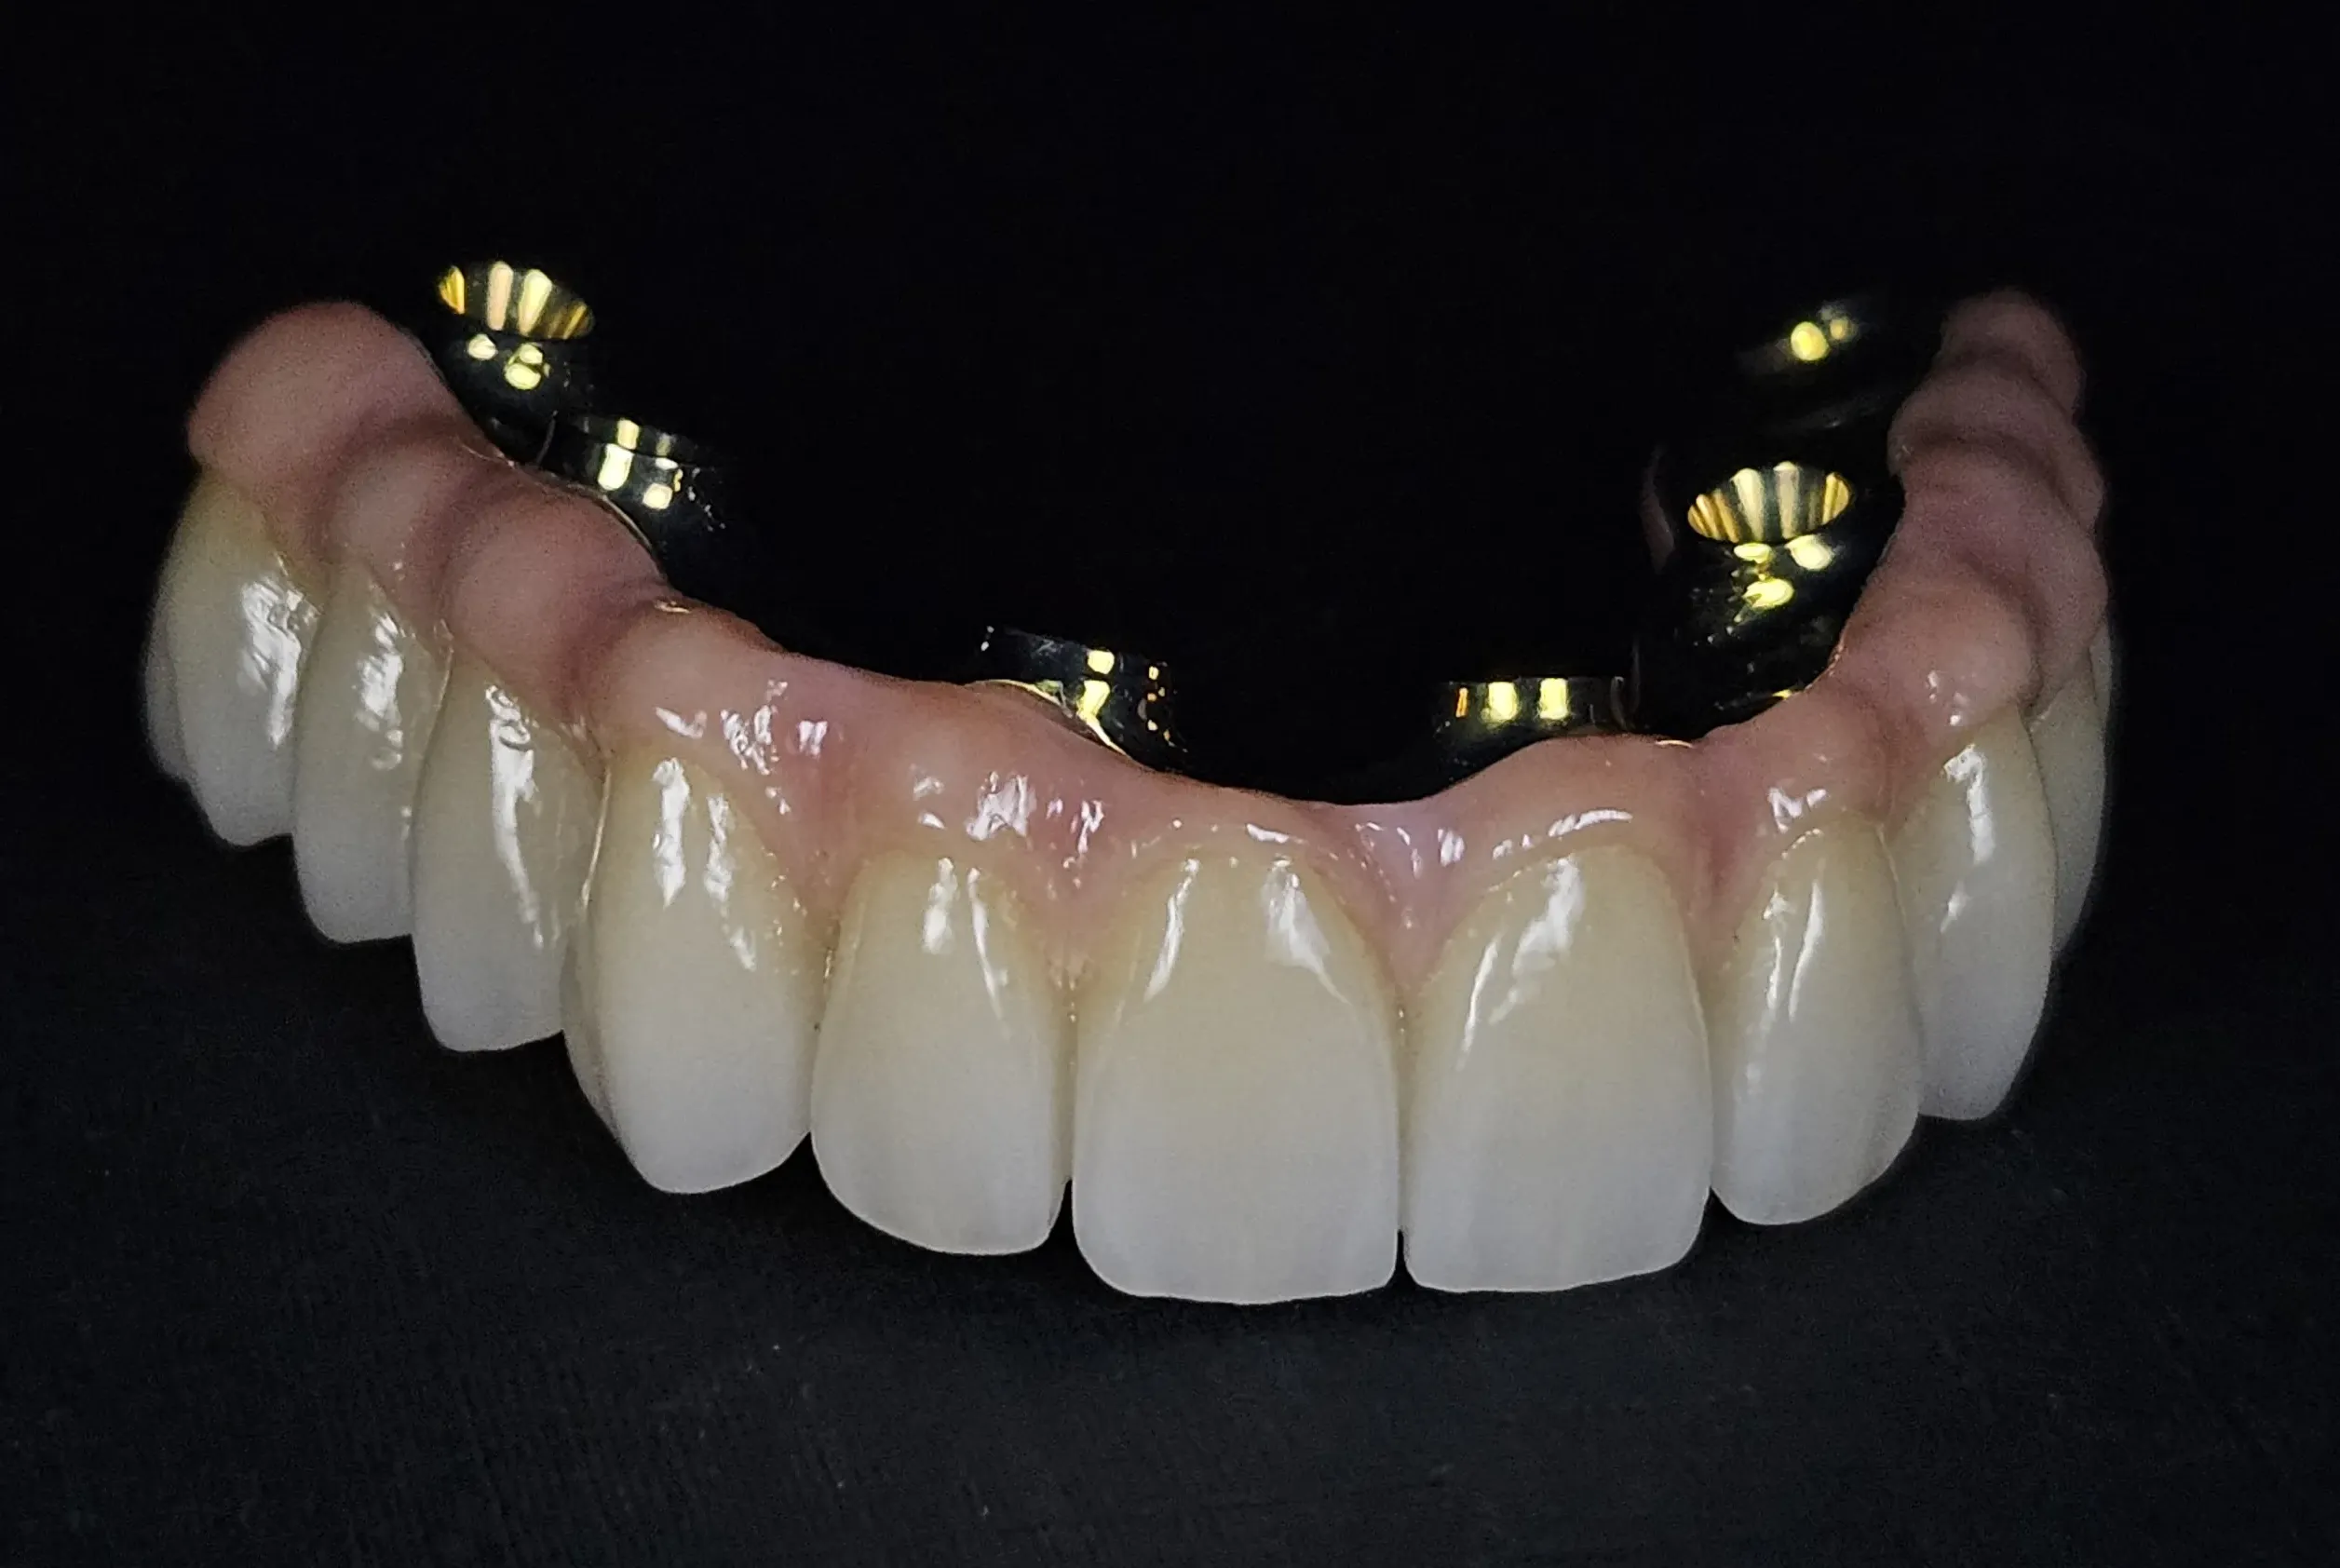

Prótesis CAD/CAM

Trabajamos con materiales de vanguardia totalmente biocompatibles y duraderos, utilizando tecnología CAD/CAM de última generación para la confección de prótesis dentales de máxima precisión y estética.